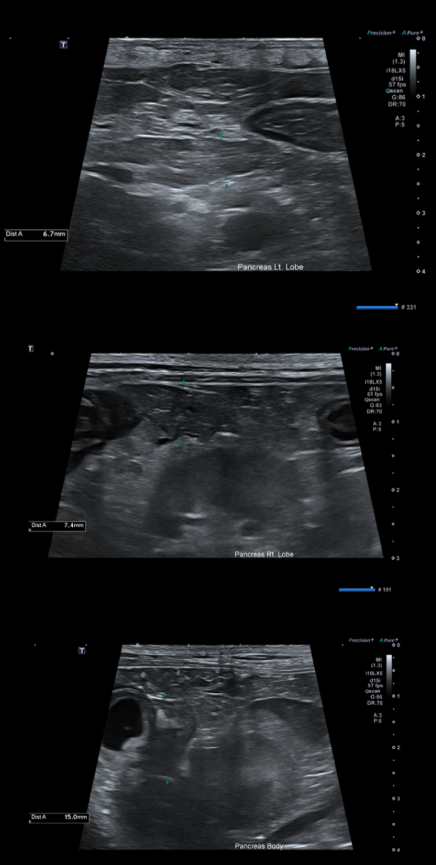

- 복부초음파

췌장의 실질은 저에코를 나타내고 있고 주변 지방은 에코가 상승되어 있습니다.

종합하였을 때 코코의 구토의 원인은 급성 췌장염으로 진단 되었습니다.

또한 복부 초음파 재검사에서 이전에 관찰되던 췌장 주변 지방의 고에코성 변화와 부종 소견이 개선되는 것으로 확인되었습니다.